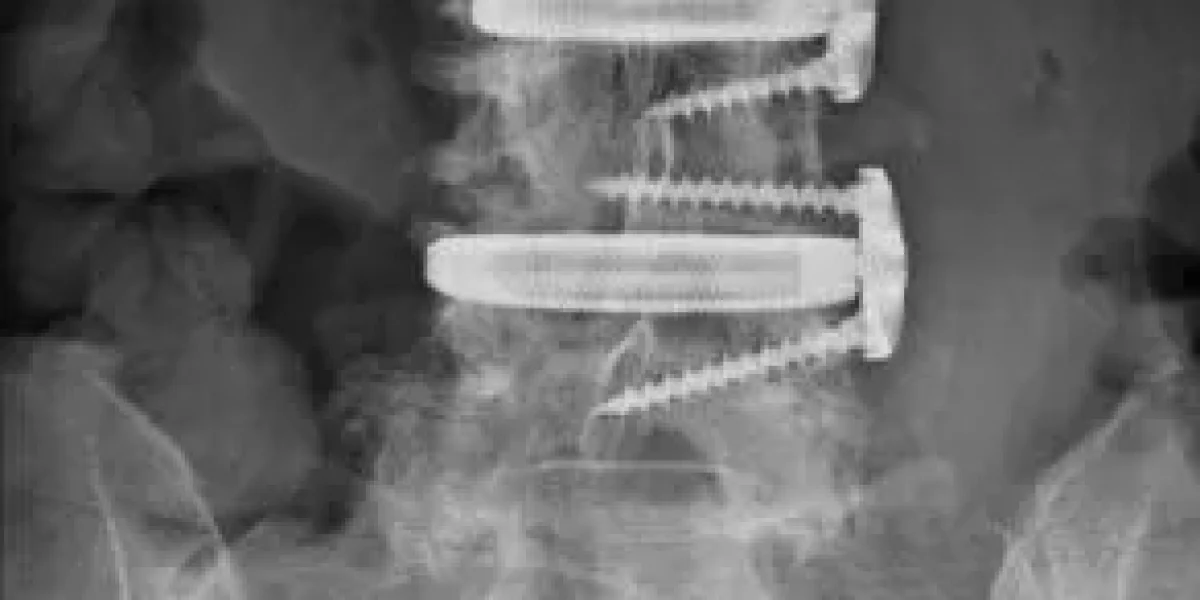

XLIF is a type of spinal fusion performed from the side of the body. This lateral approach allows the surgeon to access the spine without cutting through major back muscles. During the procedure, the surgeon removes a damaged disc and replaces it with a spacer or cage filled with bone graft material. This encourages the vertebrae to fuse, creating a single, stable bone that relieves pain and corrects deformities.

XLIF surgery relies on hardware like cages, screws, and rods to stabilize the spine while the bones fuse.

- Hardware Malposition or Failure: In some cases, the hardware can shift, break, or become loose. This may require a second surgery to correct or replace the components.

- Non-union (Pseudoarthrosis): This occurs when the vertebrae fail to fuse into a solid bone. It can lead to persistent pain and may necessitate another operation. Smoking is a major risk factor for non-union, as nicotine restricts blood flow and hinders the bone’s ability to heal.

7. Subsidence

This is when the implant or cage sinks into the adjacent vertebral bone, potentially leading to a loss of spinal correction.